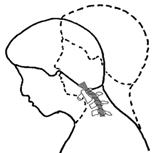

E頸椎の亜脱臼(10〜30%)

環軸椎が不安定で、脱臼を起こしやすい。

頸椎の第1番目の環椎が前方へずれる不安定な状態があると、脊髄(せきずい)が圧迫・損傷されて、

脊髄麻痺症状が出現します。

軸椎不安定性が有るときには、頸椎の亜脱臼に注意をします。

枕を入れたりしないで、頭や首を前にまげないようにします。